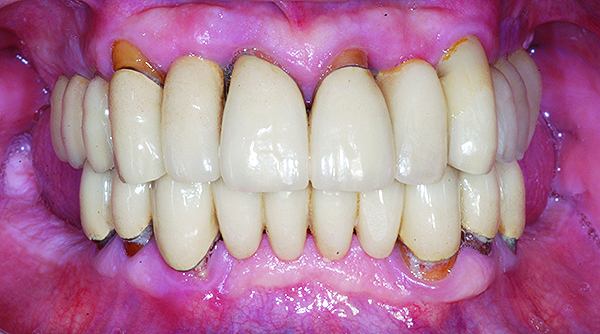

Fig 17. Intraoral frontal view of maxillary and mandibular zirconia restorations at 1.5 years.

Figure 17

The patient has been followed for continuing care since completion of the reconstruction and no complications have been reported to date (Figure 17 through Figure 20).